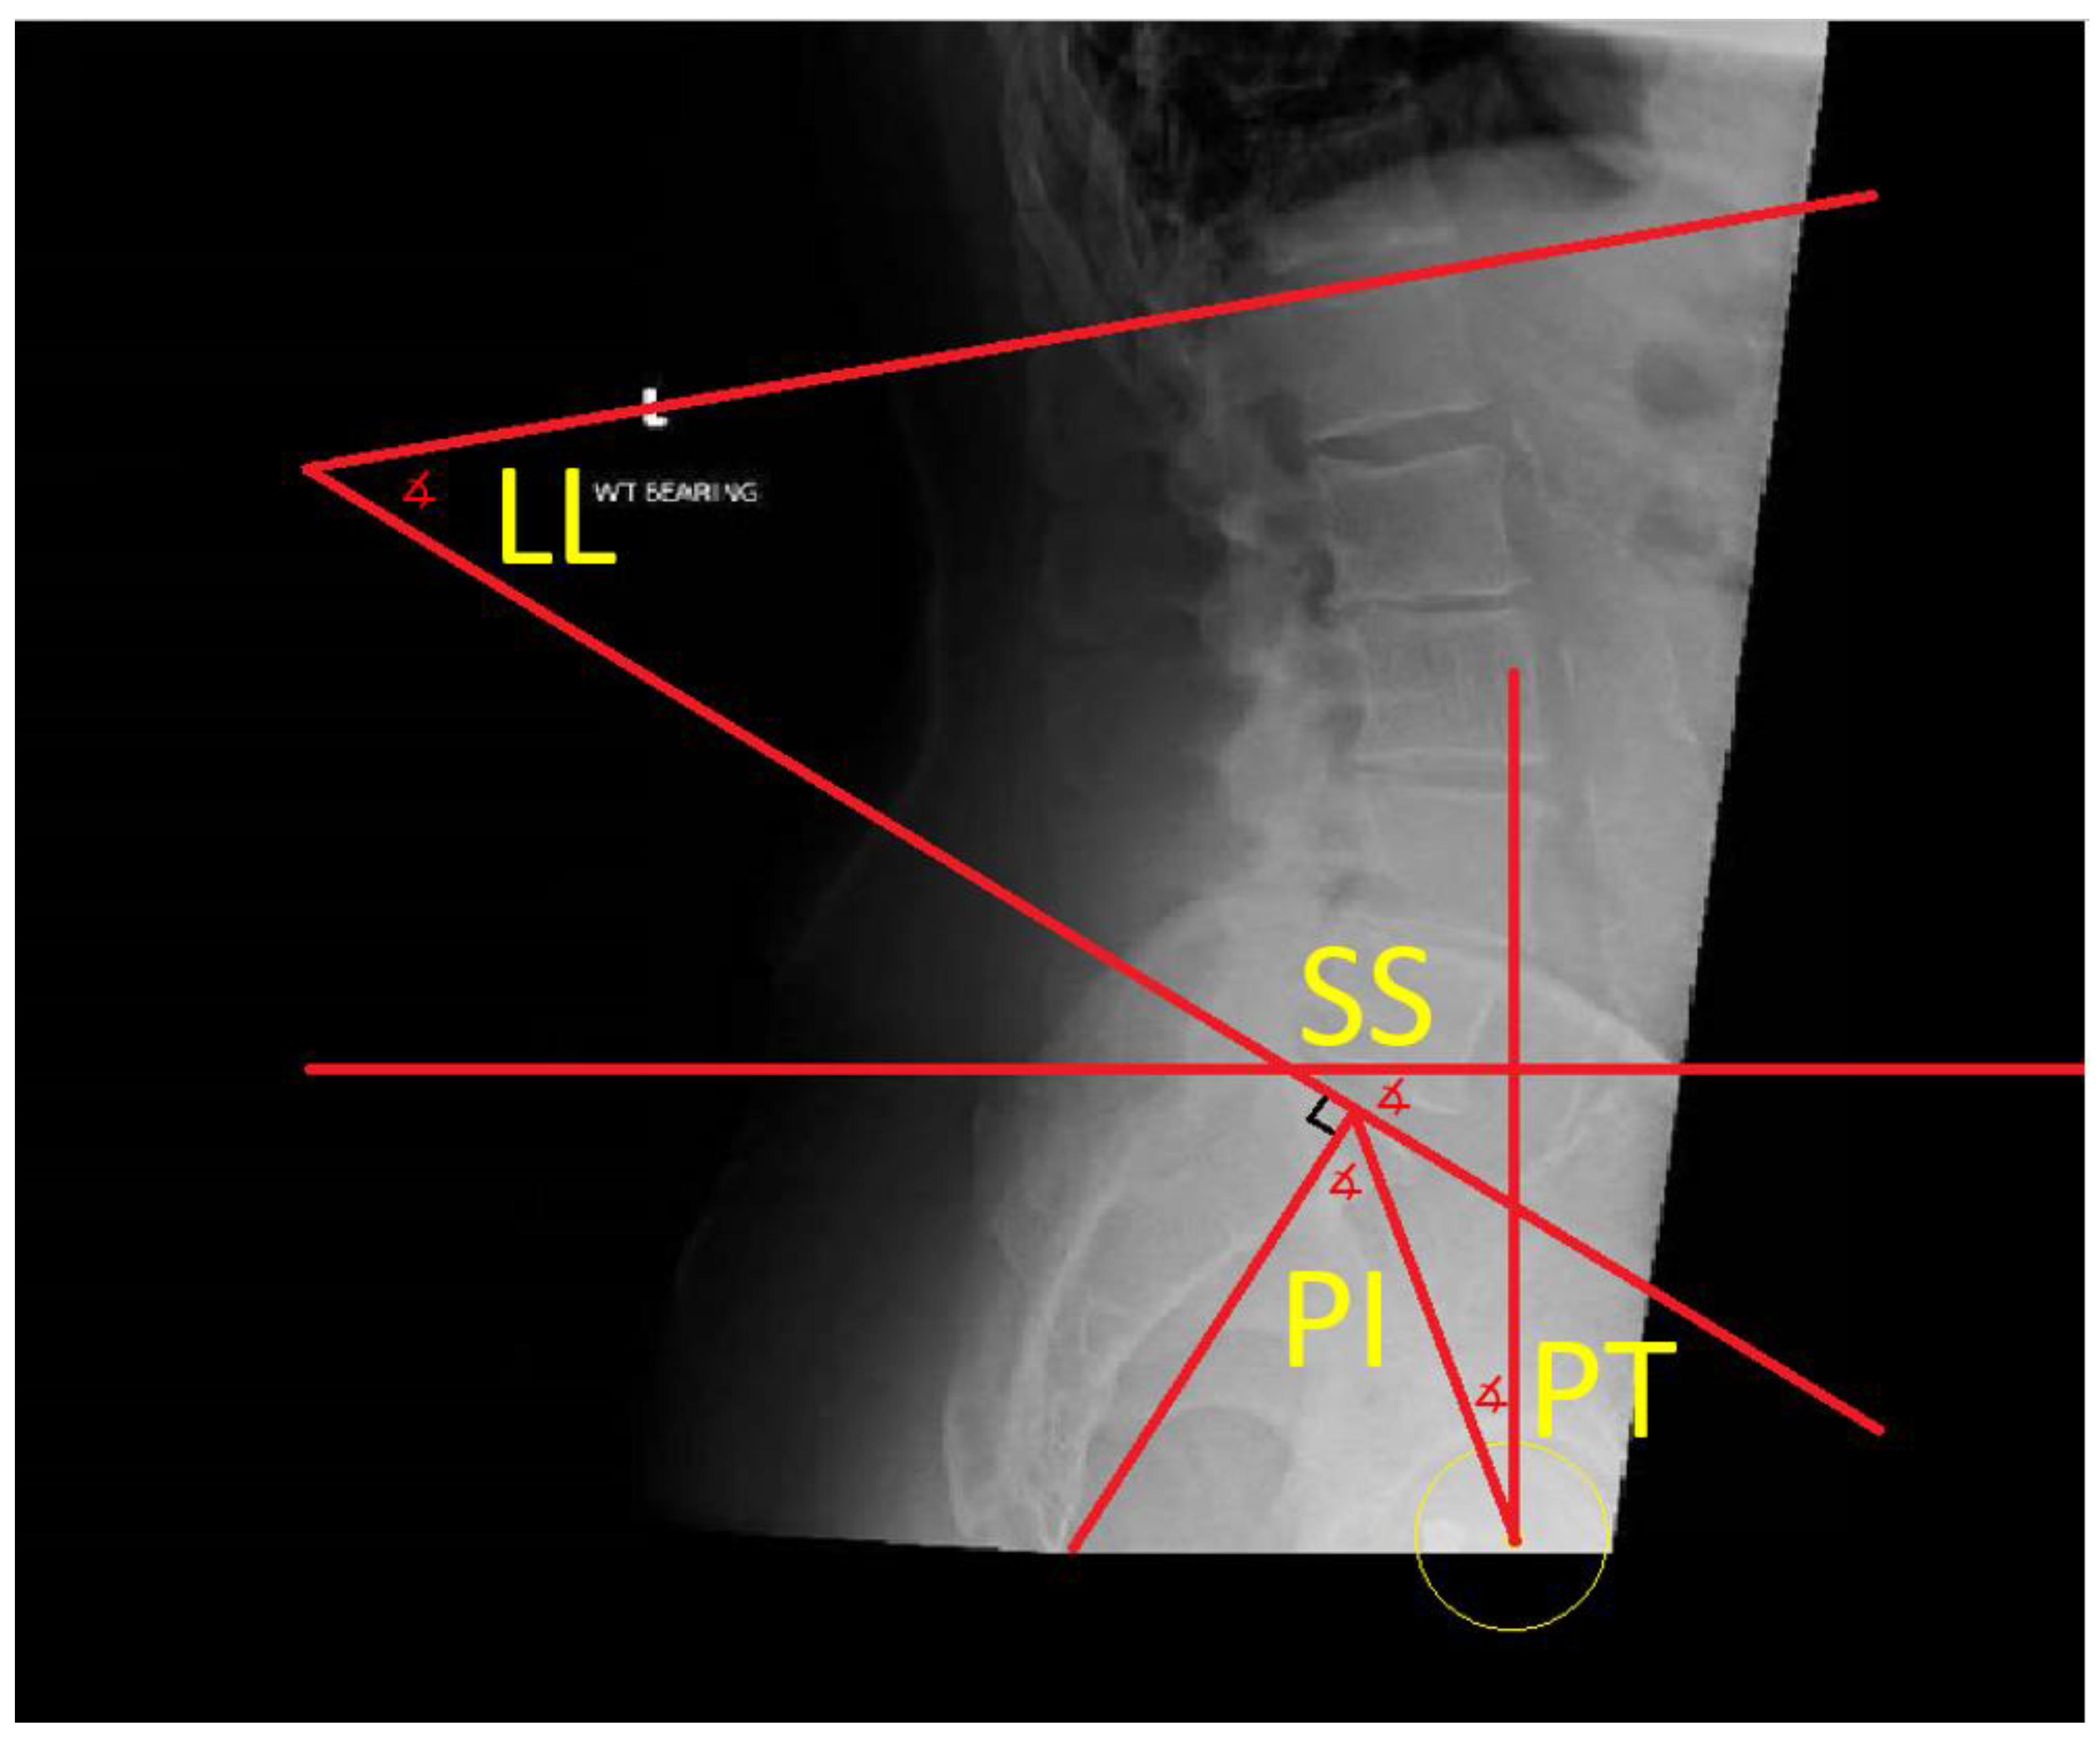

- The difference in sacral slope between standing and sitting radiographs was noted to be 6 degrees. According to the Stefl classification, this is stuck sitting, as the sacral tilt does not tilt anteriorly beyond 30 degrees with standing, indicating a high-risk patient (Figure 6a–c).